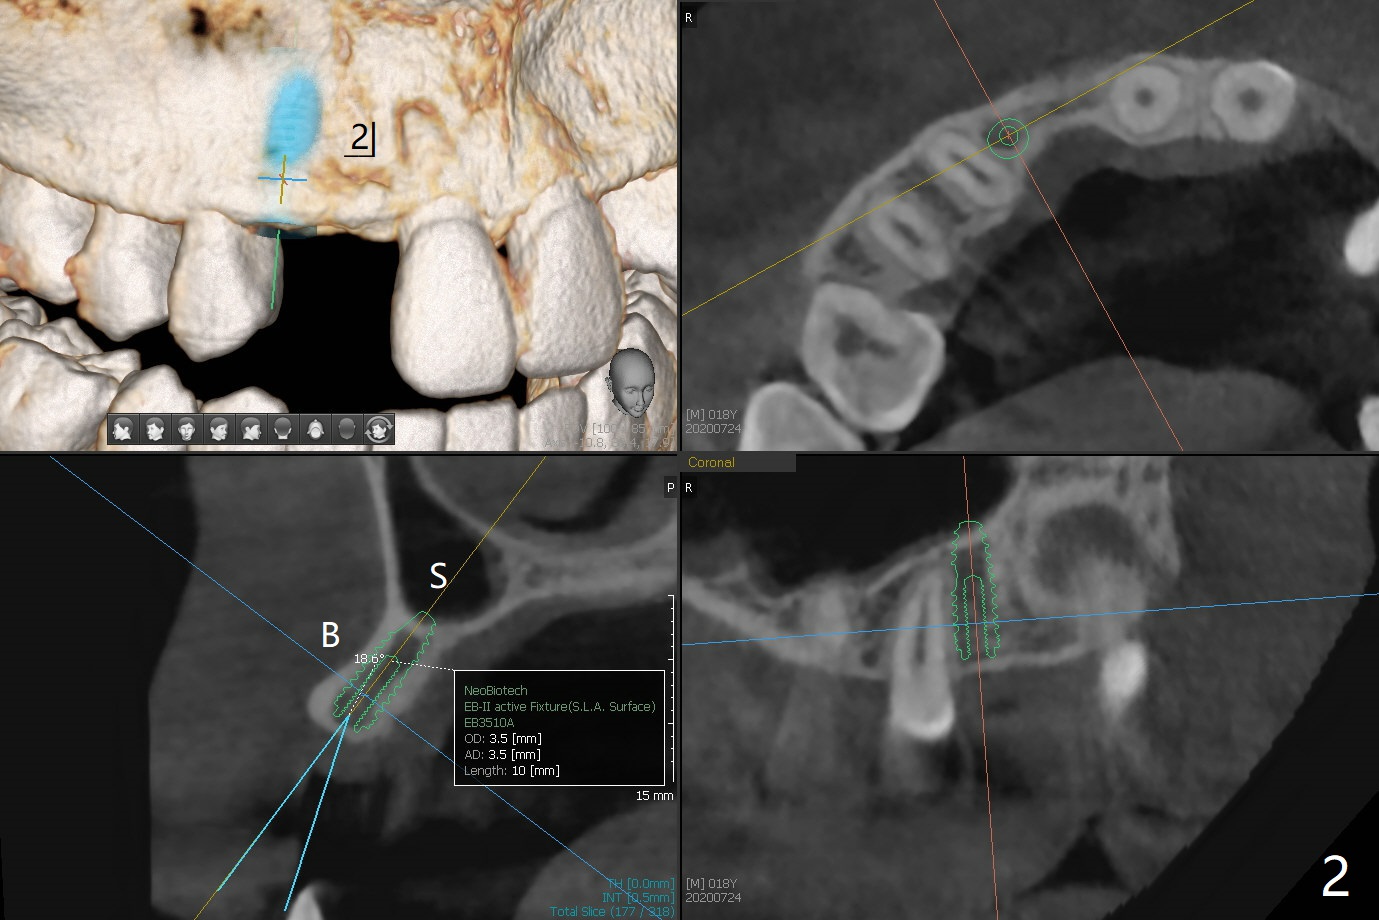

18岁男先天缺失上颌2,3(图一:双侧),2严重颊侧骨壁凹陷(图二,三:2),准备在两侧3种植(图二,三:绿色),做悬臂桥,右上植体3.5乘10毫米,但是必须用带有角度基台修复。而左上3用同样大小植体,颊侧螺纹暴露(图三 B),你会怎么处理?一个月病人到外州上学,而且治疗必须在十九岁前完成,保险可多付钱。为了能在颊侧植骨(图四红圆圈),在左上1近中做一个垂直切口(图五,六红实线),潜行分离骨膜直到4近中(红虚线),并且放置骨块,让骨膜离开颊侧骨板,钻洞时不损伤骨膜。植体放入后,检查颊侧骨块是否足够,最后放置PRF膜,缝合。